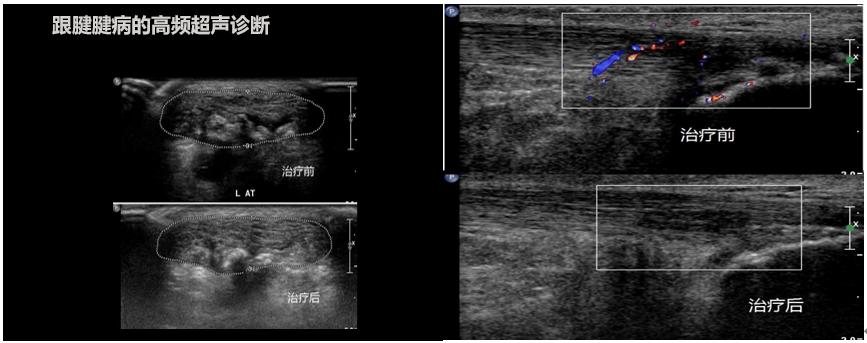

腱病治疗后超声评估跟腱断裂跟腱损伤,无论皮肤有没有破损,都建议及时

超声评估跟腱断裂应注意区分部分还是完全断裂,断端有无回缩,远端断端